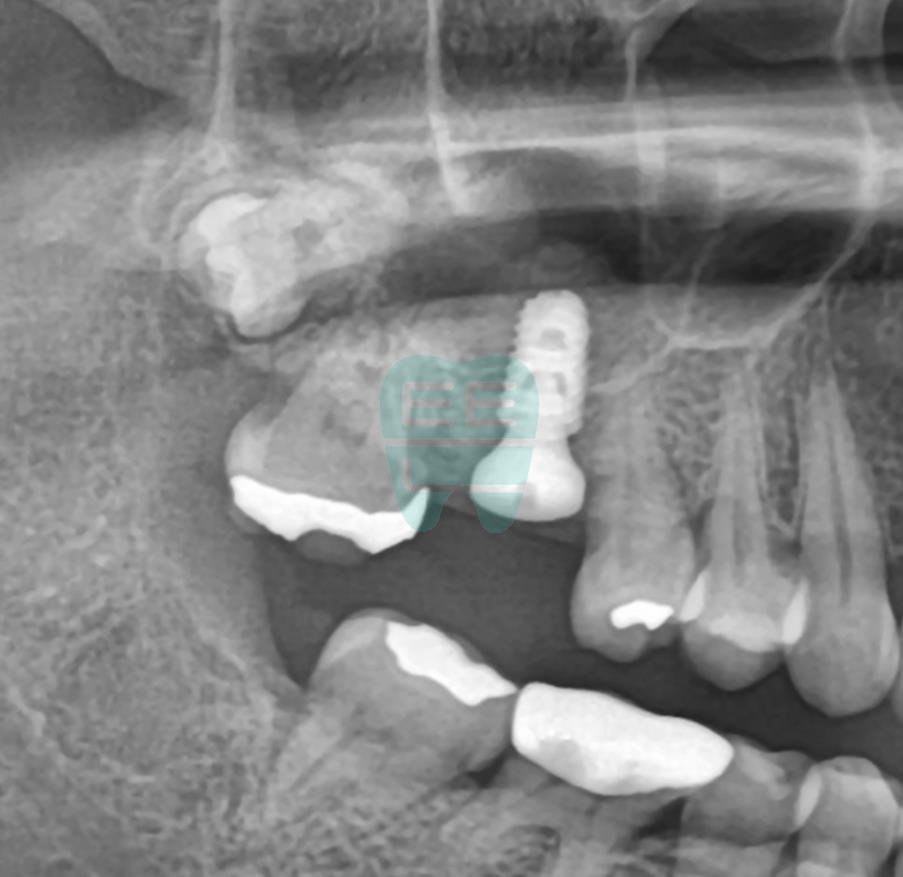

**Post-operative Panoramic X-ray** — Implant securely positioned.

**Post-operative CT Scan** — Maxillary sinus membrane safely elevated.